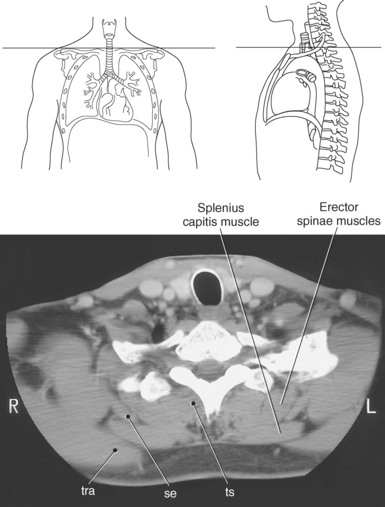

Muscles associated with respiration are the intercostal, serratus posterior superior, serratus posterior inferior, and the diaphragm (Table 6.3). The spaces between the ribs, or the intercostal spaces, are filled with three layers of intercostal muscles (external, internal, and innermost layer) (Figures 6.106 through 6.108). These muscles act together to elevate the ribs and expand the thoracic cavity, as well as keep the intercostal spaces somewhat rigid. The serratus posterior superior muscle spans from C7-T2 to ribs 2 to 5 and acts to assist forced inspiration, whereas the serratus posterior inferior muscle spans from T11-L2 to ribs 9 to 12 and acts to assist forced expiration (Figures 6.109 through 6.110). The diaphragm is a large dome-shaped muscle that spans the entire thoracic outlet and separates the thoracic cavity from the abdominal cavity (Figure 6.111). It is the chief muscle of inspiration because it enlarges the thoracic cavity vertically as the domes move inferiorly and flatten. The muscle fibers of the diaphragm converge to be inserted into a central tendon, which is situated near the center of the diaphragm immediately below the pericardium, with which it is partially blended. The diaphragm is attached to the lumbar spine via two tendinous structures termed crura (Figures 6.111 through 6.113). The right crus arises from the anterior surfaces of L1-L3, whereas the left crus arises from the corresponding parts of L1-L2 only. The left and right crura join together across the ventral aspect of the abdominal aorta to form the medial arcuate ligament. Three major openings, or hiatuses, of the diaphragm allow for the passage of vessels and organs from the thorax to the abdomen. The aortic hiatus allows for the passage of the descending aorta, azygos vein, and thoracic duct. The caval hiatus allows for the passage of the inferior vena cava and the right phrenic nerve. The esophageal hiatus allows for the passage of the esophagus and the vagus nerve.

Figure 6.110 Axial CT scan of chest with serratus posterior superior muscle.

Key: se, Serratus posterior superior; tr, trachea; rh, rhomboid muscle; in, intercostals; ts, transversospinal muscles; tra, trapezius muscle.